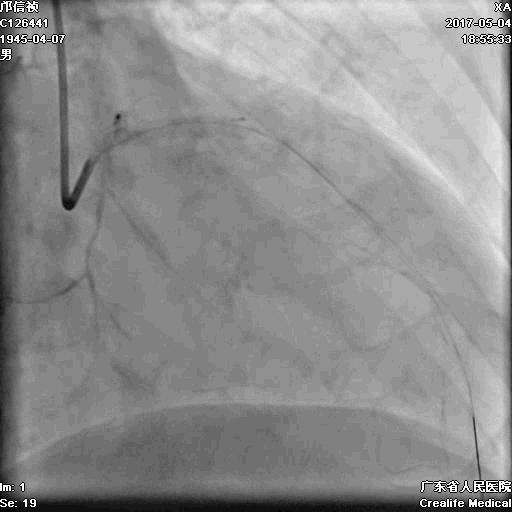

正向浅尝,改为逆向,LCX-PL

RRA:6F AL0.75 GC –RCA;

RFA:7F XB 3.5 GC—LCA 150cmcorsair

正向130cmFinecross微导管支持下尝试送PILOT150、Gaia 2导丝无法通过RCA闭塞段

SION导丝通过侧枝

逆向导丝:更换Gaia2

正向导丝:Gaia2,PILT150

正向导丝knuckle

2.5*15mm球囊扩张,逆向导丝尝试,但未能进入正向GC

1.正向2.5*15mm球囊扩张,Reverse CART

2.Guidezilla延长导管辅助下,逆向导丝进入正向GC